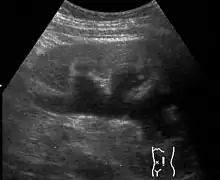

| Renal ultrasonography of hydronephrosis caused by a left ureteral stone | |

Massive hydronephrosis as marked by the arrow- Renal ultrasonography of hydronephrosis[16]